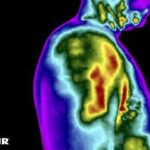

Como no caso da sequência de termogramas abaixo de um paciente do sexo masculino, 52 anos e com relato de dor em região cervical e ombro direito há mais de 1 ano. Foi realizado uma Análise Termofuncional e detectado alterações térmicas condizentes com o relato de dor.

Com estas informações, já na avaliação, foi possível determinar quais os melhores métodos e técnicas poderiam ser usados na terapia para resultados mais eficazes.